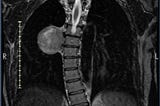

About the Tangerine in my ChestI don’t really use the word “tumor”. Instead I call it a “thing” or a “tangerine”, because the doctor said it’s the size of a tangerine…Feb 10, 2023A response icon2Feb 10, 2023A response icon2